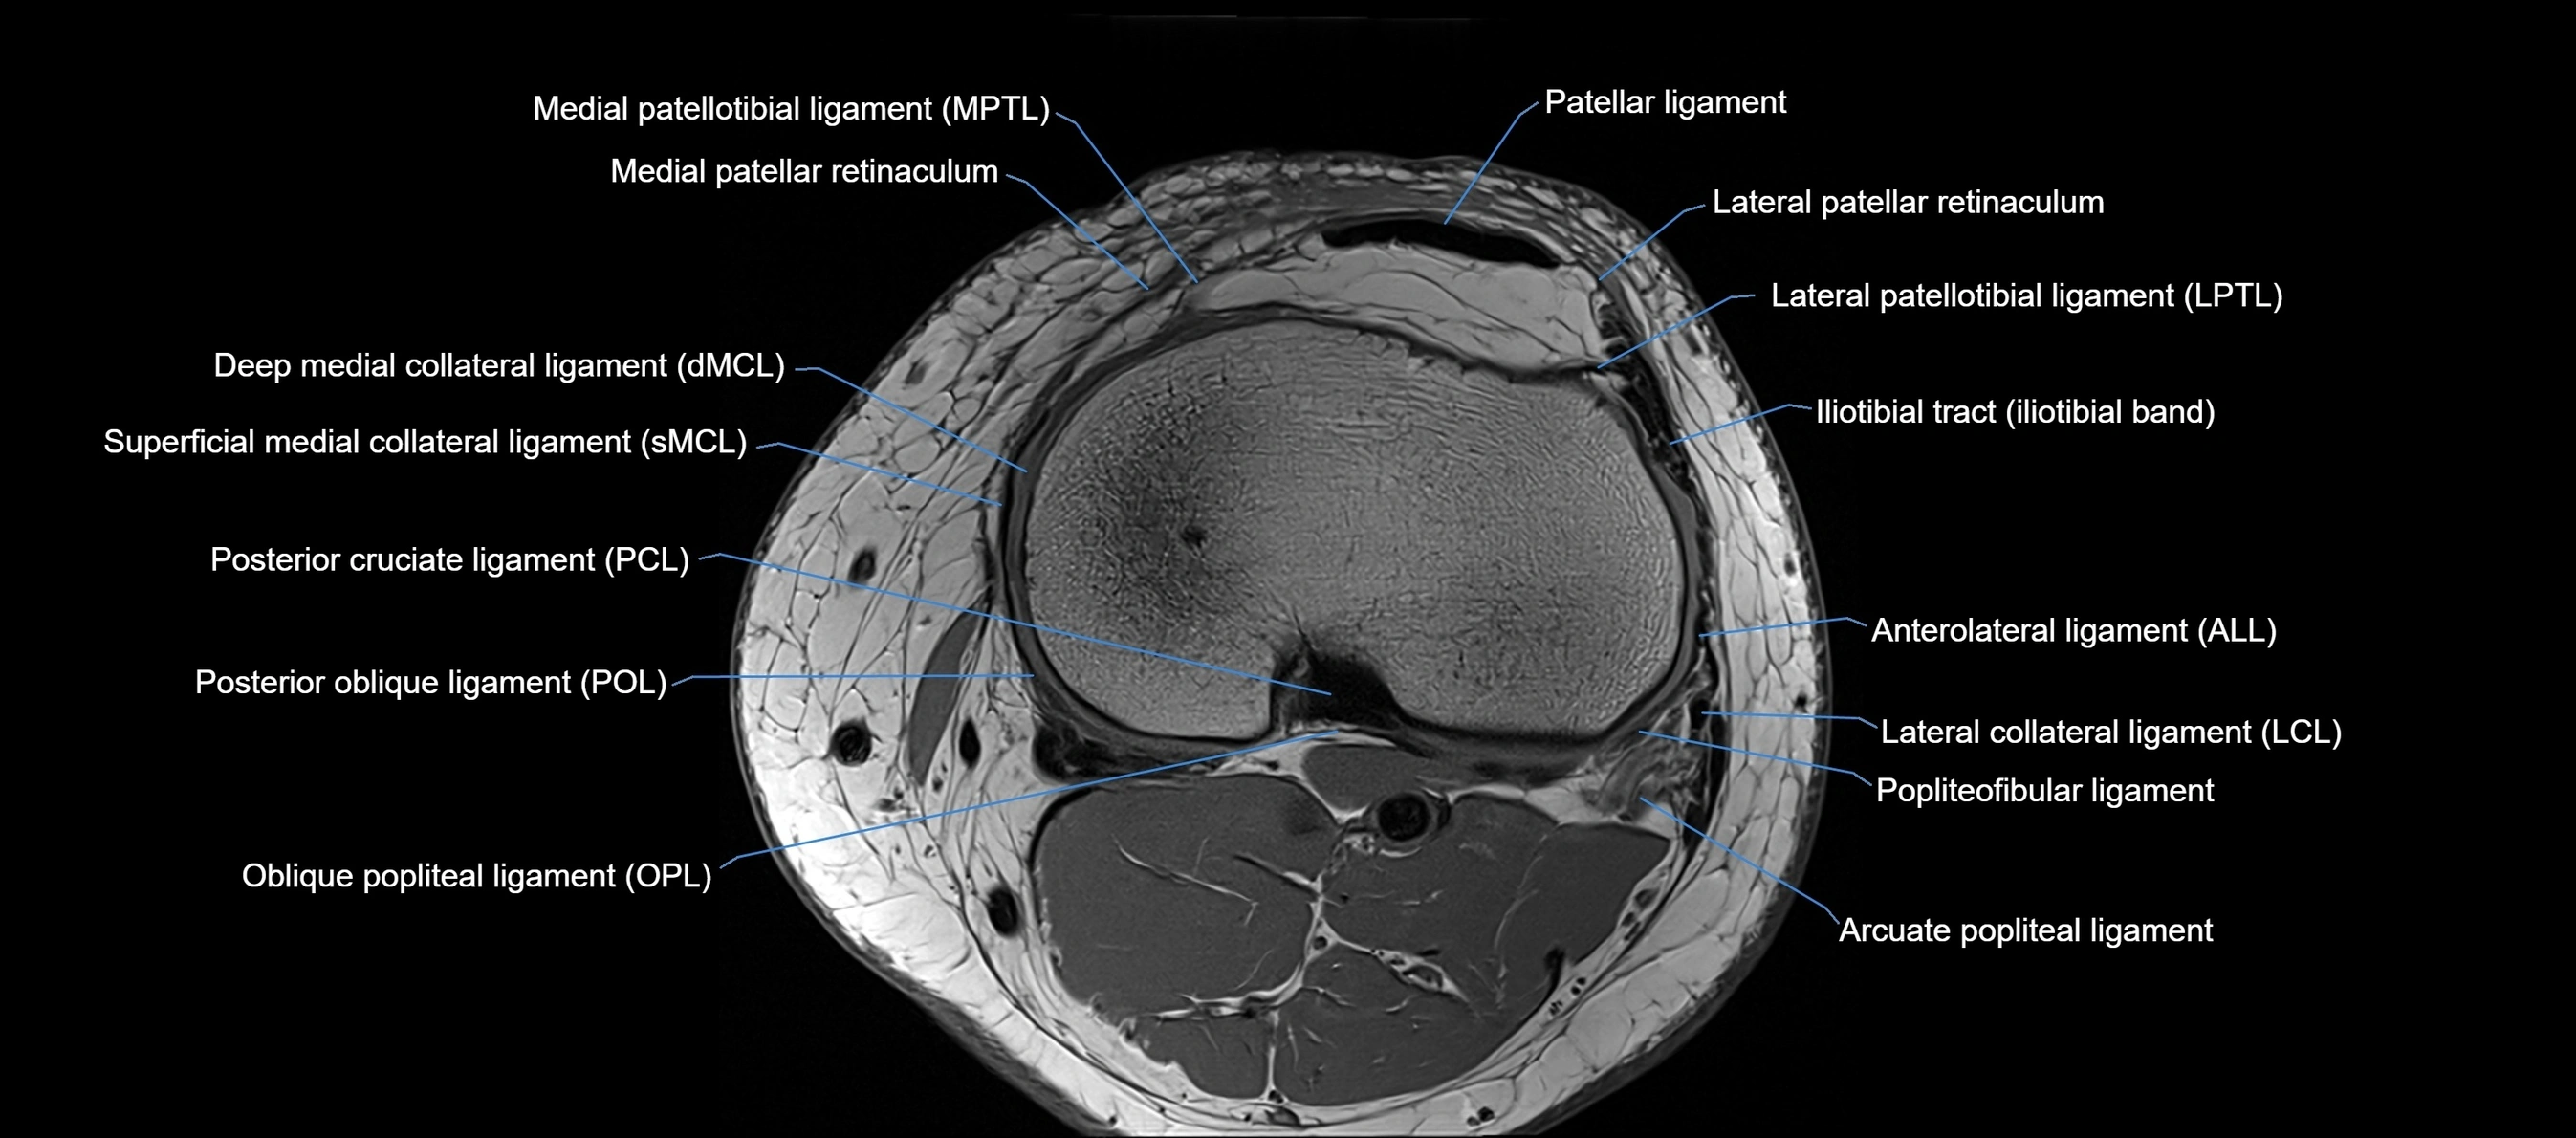

MRI images

image